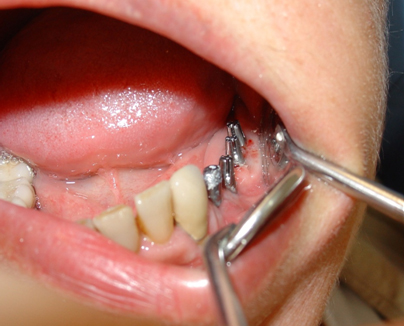

Se realiza un encerado diagnóstico en el laboratorio dental respetando los datos obtenidos durante el estudio del caso y en base al mismo se confecciona una férula quirúrgica convencional. Se colocan los cuatro implantes dentales mediante cirugía mínimamente invasiva sin colgajo. Al ser implantes dentales de una sola pieza, los muñones protéticos expuestos se fresan en boca con alta refrigeración para obtener un correcto paralelismo entre los mismos, y lograr así un ajuste sin tensiones de la prótesis fija implantosoportada.(F2)